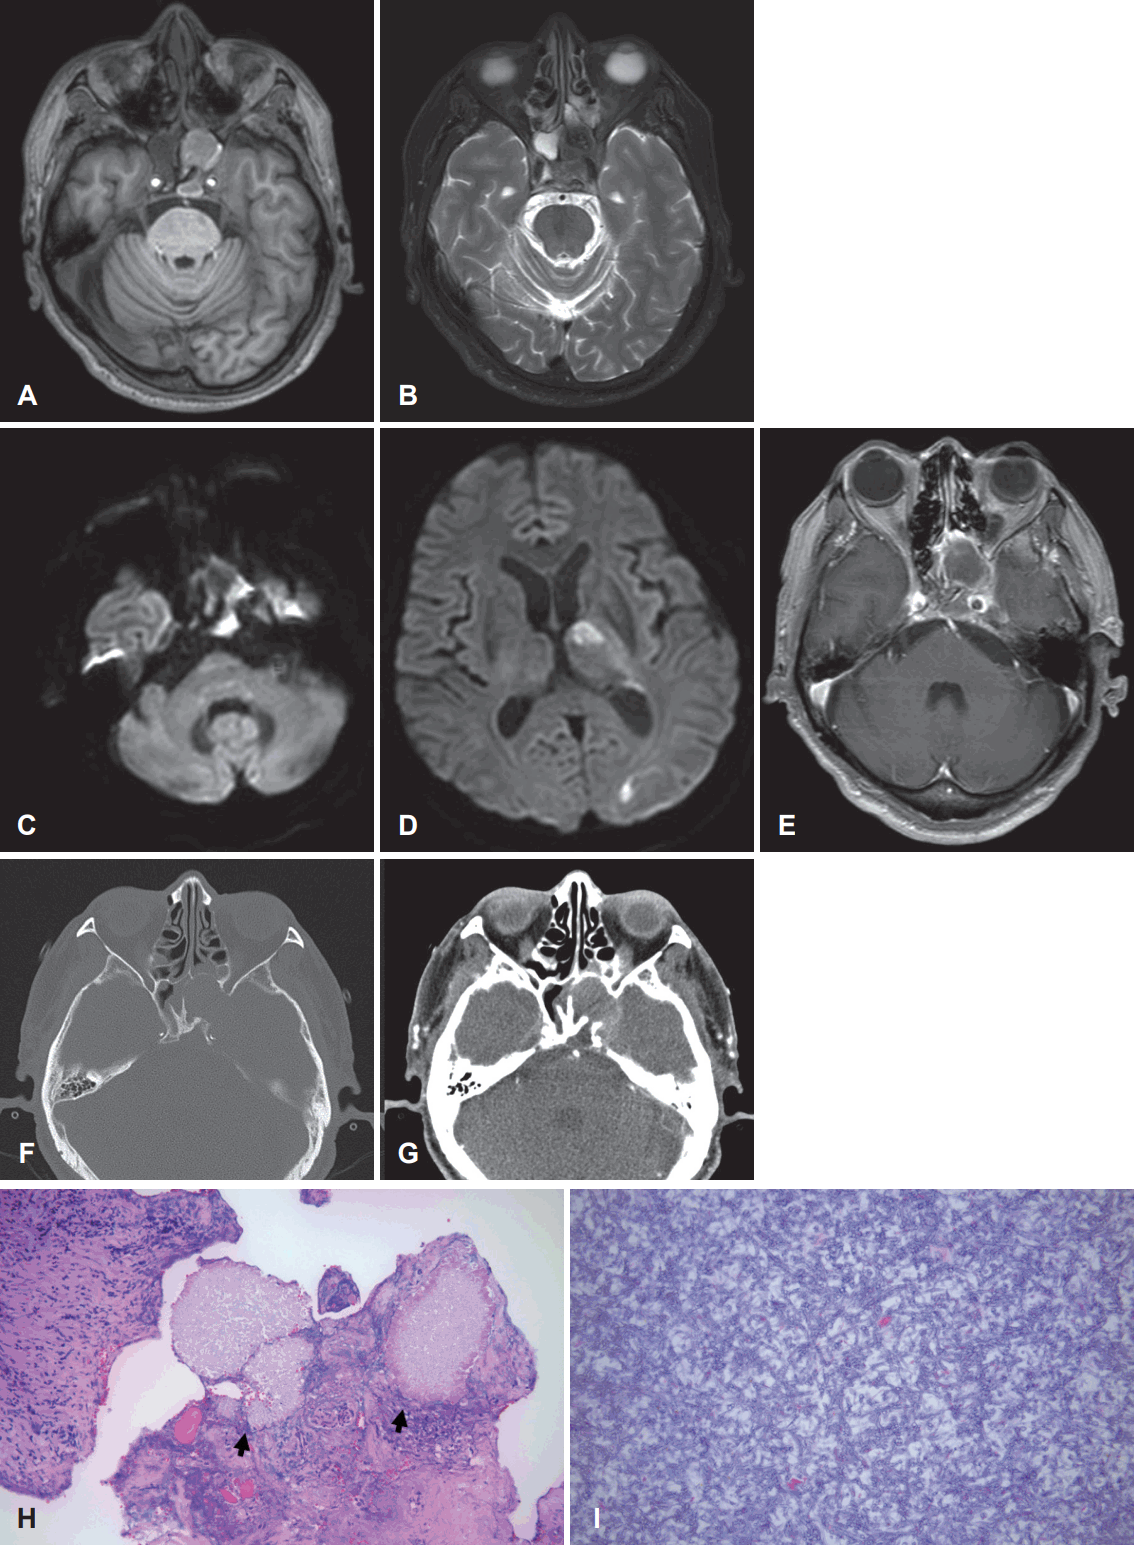

The neurology department consulted the hemato-oncology department to rule out neutropenic fever, and the patient was transferred to the hemato-oncology department for treatment. Laboratory test results for Aspergillus antigen were positive, and the patient was referred to our department to rule out invasive fungal sinusitis. A PNS CT was performed immediately, and soft density progression was seen in the right sphenoid sinus with bone erosion in the superolateral wall when compared to images taken 8 days earlier at our outpatient clinic (Fig. 3A and B). In addition, mucosal thickening had developed in the left sphenoid sinus which had not been present in previous images.

Consecutive paranasal CT and pathologic findings of a 61-year-old male who had a history of leukemia and diabetes in Case III. A: CT scan showing Mucosal thickening in the right sphenoid sinus with erosion in the skull base (red arrow). B: 8 days later. Progression of the involved site in the right sinus with mucosal thickening in the left sphenoid sinus. C and D: Presence of fungal hyphae, morphologically consistent with aspergilloma. Original magnification: C, H&E stain ×200; D, H&E stain ×400. H&E, hematoxylin and eosin.

Emergency ESS was performed and the whole sinus revealed pale cadaveric mucosa. After surgery, Voriconazole was administered as antifungal agent. Histological examination revealed fungal hyphae, morphologically consistent with aspergilloma (Fig. 3C and D). Three days after surgery, diplopia with limitation in the right lateral gaze of the right eye had developed. The patient received antifungal agent for 38 days after surgery and was discharged. He is still alive at the time of writing (28 months after surgery).

The patient in our last case was also immunocompromised and had uncontrollable localized headache. The primary physician suspected fungal infection and evaluated with a diagnosis of fungal infection in mind. However, the condition of the patient deteriorated rapidly while evaluation was in progress. Although emergency surgery was performed immediately after symptoms seemed to worsen, the infection had already progressed to a state that could not be corrected completely by surgery. Reviewing the case, when the patient had experienced uncontrollable headache even after seeing the neurologist, fungal infection could have been suspected because the patient had been immunocompromised for years. Also, if immediate CT evaluation had been performed when the patient had visited our outpatient clinic, treatment would have been administered even earlier, and better treatment outcomes would have been possible. Gillespie and O’Malley [6] reported that invasive fungal sinusitis is prevalent in people with low immunity and a diagnosis of invasive fungal sinusitis may be delayed due to ambiguous early symptoms. Therefore, it is most important to examine patients with immunocompromised status very closely and with great suspicion.